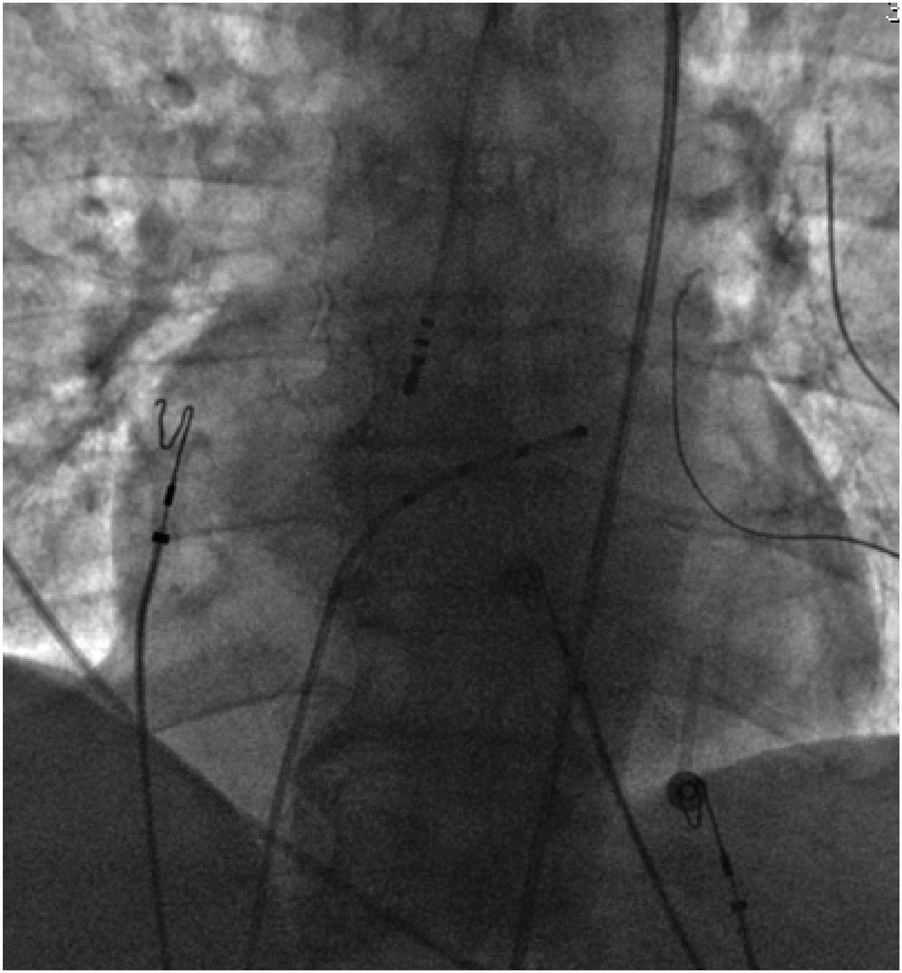

With the radiofrequency ablation power set at 30–40 W and the target temperature at 55 °C, the radiofrequency transmission lasted up to 90 s (Figure 2). During the ablation process, steam pop was not perceived, and there were no sudden changes in ablation parameters such as impedance、power or pressure values (Figure 2). After the termination of radiofrequency, the ventricular premature beats were significantly reduced. During the observation period after ablation (not immediately after), the patient suddenly complained of chest tightness, shortness of breath, and chest pain, and the blood pressure dropped to 102/65 mmHg (baseline blood pressure value: 149/78 mmHg). x-ray fluoroscopy observation showed a translucent shadow around the heart in the pericardial cavity (Figure 3), and the patient was suspected of having pericardial tamponade. Pericardial puncture and drainage were immediately performed. After slowly withdrawing 150 ml of bright red blood, no more blood was withdrawn, and the patient's blood pressure gradually recovered and tended to be stable. The ACT value immediately before pericardiocentesis was 126 s. Protamine was not administered and no additional heparin was administered due to the short duration of ablation. The unexpectedly low ACT at the time of pericardiocentesis may reflect partial heparin metabolism and consumption. Blood gas analysis of the red blood cells drawn from the pericardium suggested arterial blood. Under fluoroscopy, the translucent zone around the heart was smaller than before. In order to further clarify the perforation site, angiography was performed in the left and right ventricles(Supplementary Videos S1–S4), and it was found that the contrast agent did not extravasate outside the cardiac cavity (Figures 4A,B). Bedside transthoracic echocardiography showed that the pericardial effusion did not further increase. After indwelling the pericardial drainage tube, the patient was returned to the cardiac care unit for further observation. After 1 day of continuous drainage, no effusion was drained, and continuous review of echocardiography showed no obvious effusion (Supplementary Figures C,D). The patient was discharged after the drainage tube was removed.

Figure 3

Pericardial effusion.